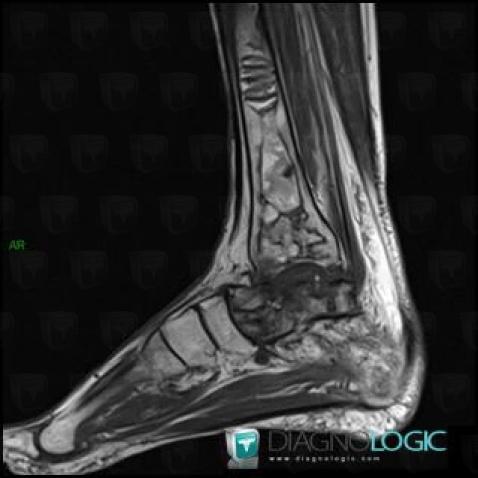

Avascular necrosis, Tibia - Distal part, MRI

Here is the specific information in the key image above:

- Diagnosis Avascular necrosis, Location(s) Tibia - Distal part, with gamuts Well-defined osteolysis, Epiphyseal osteolysis

- Diagnosis Gaucher disease, Location(s) Tibia - Distal part, with gamuts Mulltiple osteolysis

Avascular necrosis, Calcaneus, MRI

- Diagnosis Avascular necrosis, Location(s) Calcaneus, with gamuts Osteolytic lesion of calcaneus, T1 WI Hyperintense bone lesion, Lucent lesion in foot